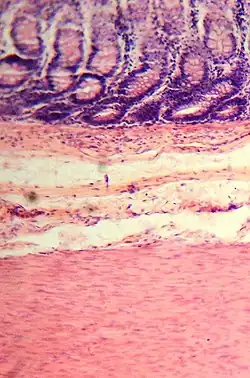

Mikroskopisches Bild der Dickdarmschleimhaut. Oben sind die Krypten angeschnitten.

Der Dickdarm zeigt den typischen Wandaufbau des Magen-Darm-Traktes mit vier Schichten. Die innerste Schicht ist eine Schleimhaut (Tunica mucosa, kurz Mukosa), die ihrerseits aus drei Schichten aufgebaut ist: die Oberfläche ist mit Epithel (Lamina epithelialis) bedeckt, das durch lockeres Bindegewebe (Lamina propria mucosae) von einer Schicht aus glatten Muskelzellen (Lamina muscularis mucosae) getrennt ist. Die Schleimhaut liegt einer lockeren Bindegewebsschicht (Tunica submucosa, kurz Submukosa) auf. Diese führt die Blut- und Lymphgefäße für die Mukosa und beinhaltet ein Nervengeflecht, den Plexus submucosus. Sie dient zudem als Verschiebeschicht zur dritten Wandschicht, der Tunica muscularis, die dem Organ mit einer inneren Ringmuskelschicht (Stratum circulare) und einer äußeren Längsmuskelschicht (Stratum longitudinale) peristaltische Bewegungen ermöglicht. Zwischen den Muskelschichten liegt ein weiteres Nervengeflecht, der Plexus myentericus, der ebenso wie der Plexus submucosus zum enterischen Nervensystem gehört. Die vierte Schicht ist je nach Abschnitt des Dickdarms entweder lockeres Bindegewebe (Adventitia) oder das Bauchfell.[21]

Ein wichtiger feinbaulicher Unterschied zum Dünndarm besteht in dem Fehlen von Darmzotten, die Dickdarmschleimhaut hat nur tiefe Krypten, die von zylinderförmigen Zellen (hochprismatisches Epithel) ausgekleidet sind. Viele dieser Zellen produzieren Gleitschleim, andere nehmen Wasser auf und dicken so den Stuhl ein. Auch die Dickdarmwand ist wie die Wand des Dünndarms in Falten geworfen. Diese entstehen aber durch örtliche Einziehungen der inneren Ringmuskelschicht, die im Querschnitt halbmondförmig erscheinen (daher der lateinische Name Plicae semilunares). Zwischen den Einziehungen bildet die Darmwand Aussackungen, die als Haustren (deutsch: Poschen) bezeichnet werden. Bei einigen Säugetieren, auch beim Menschen, ist die äußere Längsmuskelschicht zu drei kräftigen Strängen (Tänien) verdickt. An diesen Tänien hängen außen Ansammlungen von Fettgewebe (Appendices epiploicae).[22] Von diesem Muster weicht die Appendix vermiformis ab. Sie hat keine Tänien, sondern wie die anderen Abschnitte des Verdauungstraktes eine durchgehende Längsmuskelschicht. In der Lamina propria der Schleimhaut sind große Lymphfollikel zu finden.[23] Das Rektum hat statt der Tänien eine durchgehende Längsmuskelschicht, keine Haustren und keine Fettanhängsel.[24] Am Analkanal geht das Epithel des Rektums in mehrschichtig unverhorntes Plattenepithel über.[25]